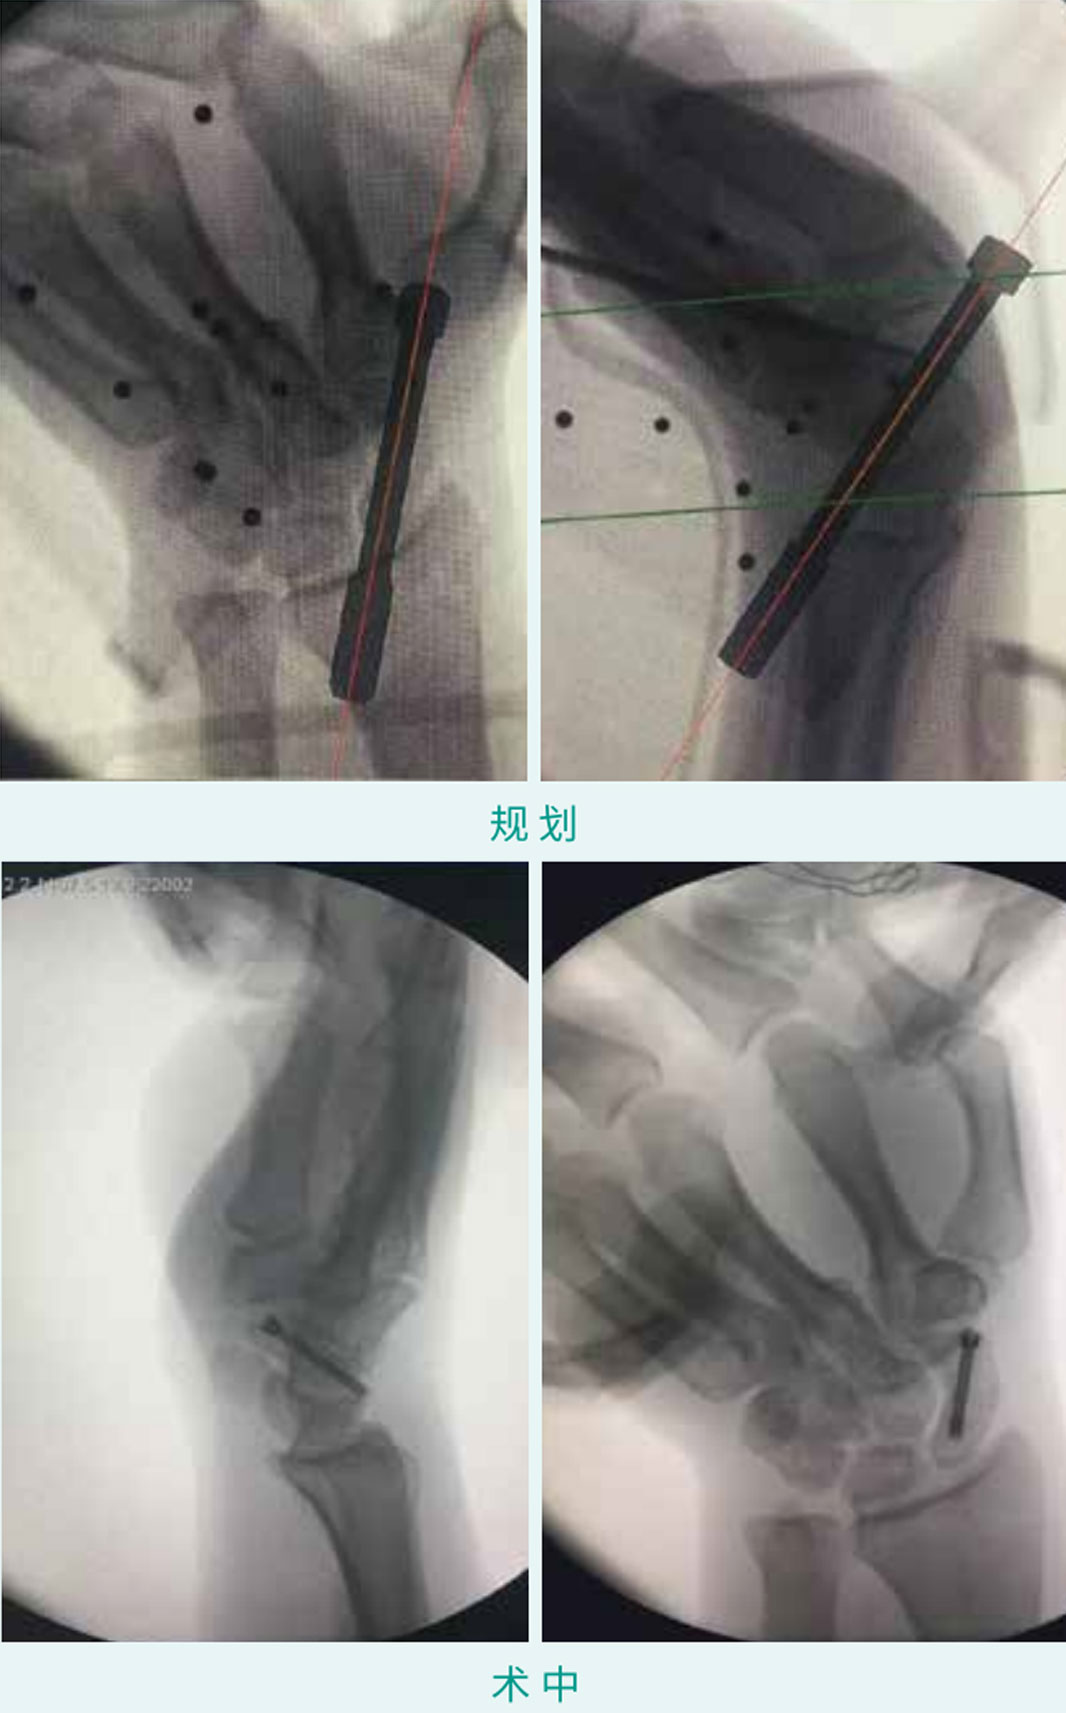

TiRobot ?  Scaphoid Fracture Percutaneous Screw Fixation

天玑? 辅助手舟骨骨折经皮空心螺钉内牢靠术

基本情形:患者男 ,27岁 ,手舟骨骨折

机械人累积用时:15分钟

植入物:1枚空心螺钉

病例泉源:克拉玛依市中心医院 廖燚 汪少波 毛峰 张德华